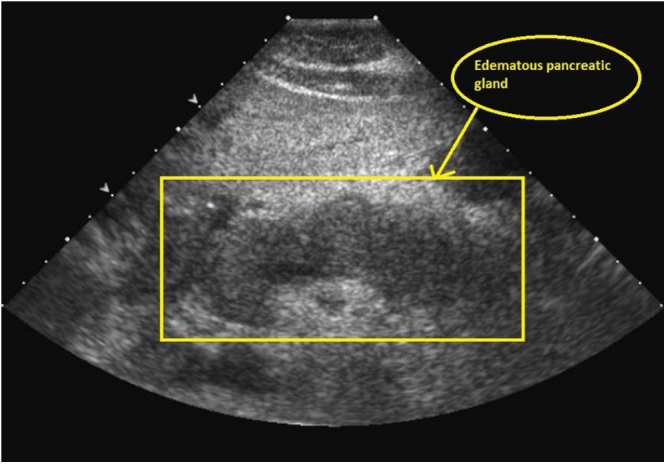

Presentation of case: A 26-year-old female, G4P1L1A2 at 36 weeks and 3 days of gestation, presented with an acute onset of abdominal pain in the epigastric region and multiple episodes of vomiting. With a diagnosis of acute pancreatitis, she was admitted to the intensive care unit for the multidisciplinary approach with a plan to reduce the triglyceride (TG) levels rapidly. The woman was finally discharged against medical advice with oral antibiotics.

Case discussion: Hypertriglyceridemia-induced acute pancreatitis in a pregnancy is a rare occurrence, usually seen in females with prior hyperlipidemia and with genetic predisposition, which is associated with significant morbidity and mortality. Our patient presented with TG levels above 1500 mg/dL. The favored treatment modality in our case was insulin therapy and omega-3 fatty acids. Baby was delivered through an elective caesarean section.